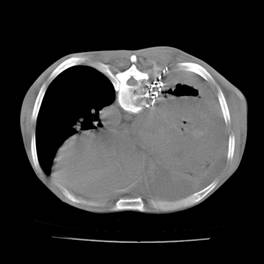

典型病例2:患者张XX,男,65岁,住院号:496686,因发热、胸闷、背痛2月余入院,体温最高达39℃,背部疼痛难忍。2015年6月29日胸部增强CT示:右肺下叶11.6cmx12.5cm巨大肿块,中心大片低密度坏死区,第8胸椎及右侧第8后肋骨转移。于7月2日行CT引导下穿刺活检术,病理证实为右肺鳞癌。给予125I放射性粒子植入治疗,术中首先利用植入针,穿刺肿块中央坏死区,连接引流袋后抽出肿瘤内坏死液体约500ml,抽液后肿瘤缩小约1/3;随后将125I粒子植入到第8胸椎体及第8后肋骨转移区,同时重点放置患侧滋养动脉供血区域。术后第二天,患者体温恢复正常;术后一周随访,患者背痛缓解。该患者出院回家,仍在随访中。

术前CT片